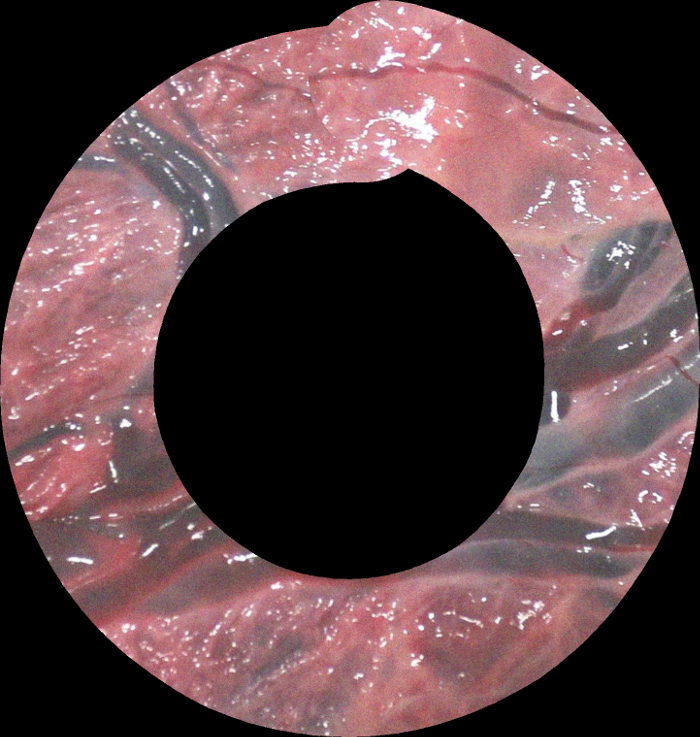

Mosaics generated using the proposed DSM for the EX, PHN1, PHN2 and INVI sequences are shown in Fig. 5. These mosaics are best assessed in the supplemental video that shows the qualitative comparison with respect to FEAT and DIH. DSM created a meaningful mosaic for EX (unseen data) with minimum drift accumulation over time which can be observed from the start and end frames in Fig. 5(a). PHN1 contained non-planar views without occlusions with a freehand circular trajectory. DSM generated reliable mosaics with minimum drift (Fig. 5(b)), however FEAT drifted away due to non-planar views, insufficient feature matches and long-range videos. PHN2 and INVI represent the most challenging scenarios containing highly non-planar views with heavy occlusions, low resolution and texture paucity. We observe from Fig. 5(c)(d) that although the generated mosaics can serve well for increasing the FoV, yet there is a noticeable drift due to highly challenging conditions. Such errors may be corrected by end-to-end training using the photometric loss [8].